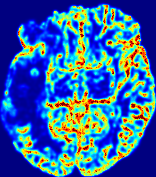

Slice #1Slice #2Slice #3Slice #4Slice #5Slice #6𝐕gt2subscriptnormsuperscript𝐕gt2\|{\bf{V}}^{\text{gt}}\|_{2}Refer to captionRefer to captionRefer to captionRefer to captionRefer to captionRefer to caption(a)Refer to captionRefer to captionRefer to captionRefer to captionRefer to captionRefer to caption(b)Refer to captionRefer to captionRefer to captionRefer to captionRefer to captionRefer to caption(c)Refer to captionRefer to captionRefer to captionRefer to captionRefer to captionRefer to caption(d)Refer to captionRefer to captionRefer to captionRefer to captionRefer to captionRefer to caption(e)Refer to captionRefer to captionRefer to captionRefer to captionRefer to captionRefer to caption(f)Refer to captionRefer to captionRefer to captionRefer to captionRefer to captionRefer to captionRefer to caption000.30.30.30.60.60.60.90.90.91.21.21.21.51.51.5(mm/s)𝑚𝑚𝑠(mm/s)

Figure 12: PIANO effectiveness and robustness testing: advection imaging via advection. Top row shows the ground truth 𝐕gt2subscriptnormsuperscript𝐕gt2\|{\bf{V}}^{\text{gt}}\|_{2} used for simulating pure advection. (a)-(f) refer to the results for 𝐕2subscriptnorm𝐕2\|{\bf{V}}\|_{2} estimated by PIANO, with simulated advection imaging series where Rician noise at levels 0%, 2%, 4%, 6%, 8%, 10% was added respectively.

We further simulate noisy concentrations by adding Rician noise [24] with variances equalling 2%, 4%, 6%, 8%, 10% of the originally simulated concentrations {Cti}superscript𝐶subscript𝑡𝑖\{C^{t_{i}}\}. We then test how well PIANO can estimate the underlying velocity field via Eq. 15 with the same model settings (except without estimating the diffusion) as in Sec. 3 given the original and the noisy concentration time-series. Fig. 12 shows the estimated 𝐕est2subscriptnormsuperscript𝐕est2\|{\bf{V}}^{\text{est}}\|_{2} for one patient. Fig. 11 (a) shows the summarized estimation results for all 43 patients. PIANO almost perfectly captures the underlying velocity field, and maintains excellent performance even when estimating from concentrations with varying noise levels.